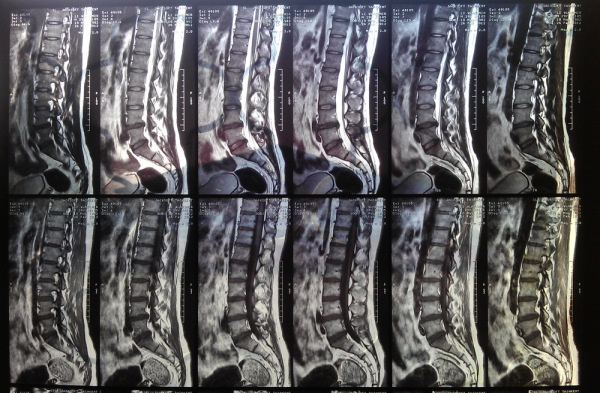

МРТ пояснично-крестцового отдела очень информативен в области диагностики патологий, при которых развиваются дегенеративно-дистрофические процессы. Вовремя поставленный диагноз помогает начать своевременное лечение и даже поставить на ноги пациента, который потерял на это надежду.

Врачи отмечают, что магнитно-резонансная томография позвоночника является одним из самых информативных методов диагностики заболеваний этой области. Она позволяет получить детализированные изображения мягких тканей, межпозвоночных дисков и нервных корешков, что особенно важно при подозрении на грыжи, остеохондроз или воспалительные процессы. Специалисты подчеркивают, что МРТ не использует ионизирующее излучение, что делает его безопасным для пациентов. Однако, несмотря на высокую точность, результаты МРТ должны интерпретироваться в контексте клинической картины и других исследований. Врачи рекомендуют проводить МРТ при наличии специфических симптомов, таких как боль в спине, онемение или слабость в конечностях, чтобы обеспечить своевременное и адекватное лечение.

МРТ создаёт подробные изображения вашего позвоночника. МРТ позволяет выявить большинство травм позвоночника, а также возрастные изменения. Даже незначительные проблемы или изменения, не являющиеся причиной боли в спине, могут быть выявлены. Эти результаты редко влияют на первоначальное лечение, назначенное врачом.